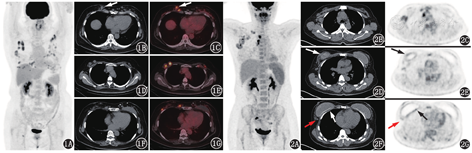

患者女,59岁,体格检查发现右乳肿物2个月。患者2个月前体格检查行胸部CT发现右乳肿物,自述右乳偶有疼痛。进一步行钼靶提示右乳腺内下象限距乳头约40 mm处大小18 mm×12 mm肿块[乳腺影像报告数据系统(breast imaging reporting and data system, BI-RADS) 4B类],左乳腺内下象限粗大钙化灶,双侧腋下多发致密影。乳腺超声提示相同位置低回声团,边界欠清、形态不规则、回声欠均,BI-RADS 4B类;另双侧乳腺腺体层旁可见多个低回声团,范围较广。患者20余年前行双乳聚丙烯酰胺水凝胶(奥美定)注射式丰胸,14年前行双乳奥美定取出手术。为评估乳腺病变性质行18F-FDG PET/CT显像(图1),可见乳腺超声及钼靶提示的右乳内下象限结节为高代谢,大小1.9 cm×1.4 cm,SUVmax为3.9;此外可见左侧乳腺假体影,双侧胸壁皮下、肌间、左乳假体表面广泛分布大量软组织结节,边界尚清晰,代谢不同程度增高,多伴钙化,代谢程度与右乳内下象限结节相似或更高,SUVmax为6.5;双侧腋下、内乳淋巴链未见明确代谢增高或肿大淋巴结。结合患者有乳腺假体植入病史,双乳及胸壁结节分布广泛、多发、形态规则、明显钙化等特征,可判定这些结节很可能为炎性结节,而右乳内下象限病灶可能与其他结节性质相同,也有可能为其他性质病变,单从PET/CT上无法完全明确。之后患者进行了超声定位下右乳肿物局部扩大切除活组织检查(简称活检),病理提示炎性坏死结节,伴炎性细胞浸润、陈旧性出血、多核巨细胞反应及钙化,未见癌。结合病理结果,考虑双侧乳腺及胸壁结节均为乳房假体植入相关的炎性结节。